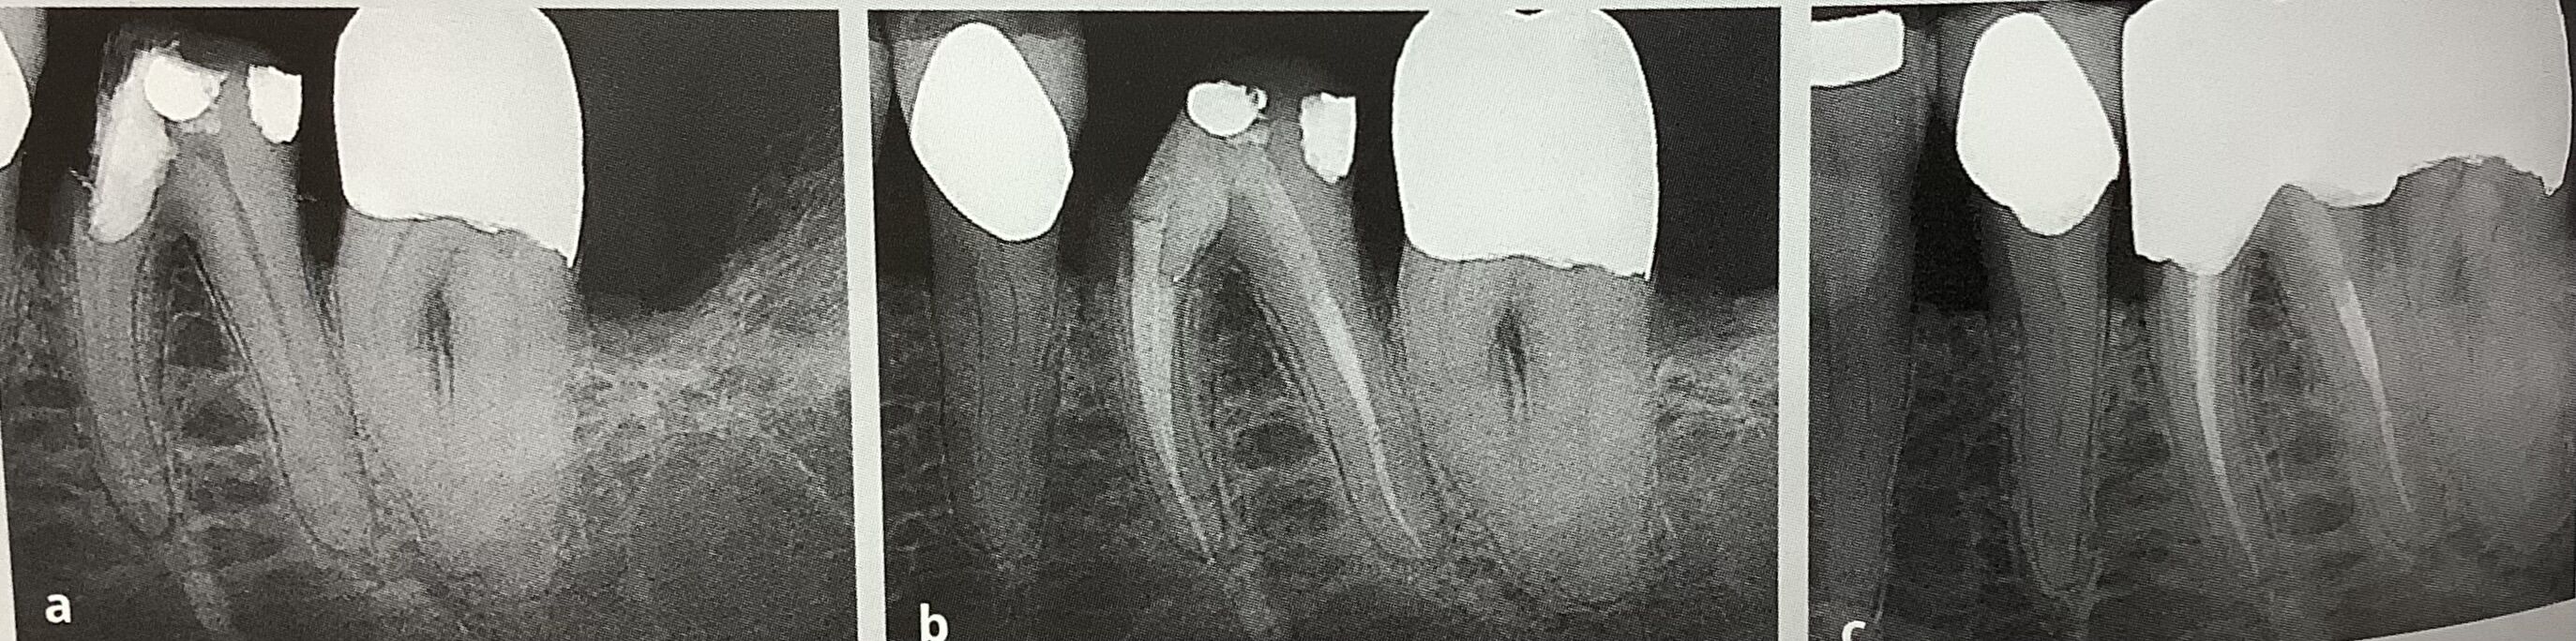

バイトウイング、咬翼法、上下の奥歯を咬んだ状態で真横から撮る方法です。

この方法が残っている歯を状態を見るには、一番です。

神経の部屋、歯髄腔の状態、

歯を被せられる?に大切な歯頚部、歯の頭と根っこの継ぎ目、ウエスト部分の状態、

虫歯がどこまで進んでいるのか?

特に根っこにまで進んでいるのか?骨の近くや根っこの分かれ目に近いのか?を見る時にです。

歯はウエスト部分の下が細くなっているので、

たった1ミリ、根の下へ虫歯が進んだだけで、急激に歯の厚みが薄くなってしまいます。

真ん中のが、バイトウイング法です。根元部分や神経の頭の部屋などが、よく分かります。

歯の間の虫歯を調べるには、1番です。

左のレントゲンでは、黒い虫歯が大きくて残せないかも?

でも真ん中から、まだ骨や分岐部、根っこの分かれ目まで進んでいないと分かります。

なので根管治療をして残す事ができました。